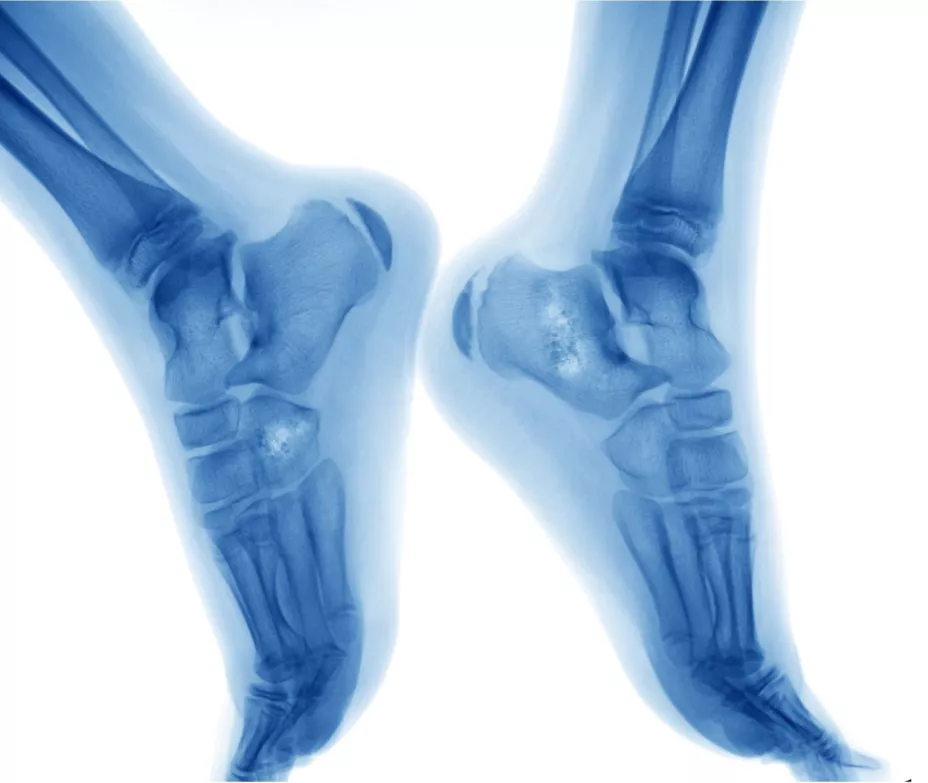

Indicó que la Organización Mundial de la Salud (OMS) ha descrito más de 100 tipos de sarcoma que se alojan principalmente en músculo, tejido graso o hueso; también está asociado a infecciones y a pacientes con inmunodeficiencia, “cada uno tiene un abordaje y tratamiento diferente”.

“Entre más temprano se haga el diagnóstico y el abordaje, mejor le va a ir al paciente, es indispensable el tratamiento quirúrgico para poder lograr el mejor resultado y esto es posible en las etapas tempranas, cuando el tumor se encuentra extendido es más difícil dar un abordaje quirúrgico completo e incluso cuando se presenta en una extremidad, que no se tenga que llegar a la amputación”, enfatizó.